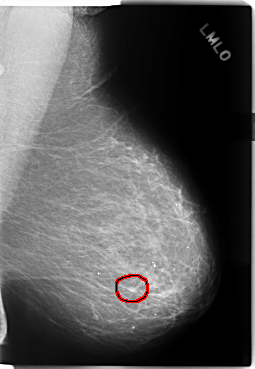

C_0205_1.LEFT_CC

LEFT_CC LINES 5856 PIXELS_PER_LINE 3496 BITS_PER_PIXEL 12 RESOLUTION 50 OVERLAY

FILE: C_0205_1.LEFT_CC.OVERLAY

TOTAL_ABNORMALITIES 1

ABNORMALITY 1

LESION_TYPE MASS SHAPE IRREGULAR MARGINS SPICULATED

ASSESSMENT 4

SUBTLETY 4

PATHOLOGY MALIGNANT

TOTAL_OUTLINES 1

BOUNDARY